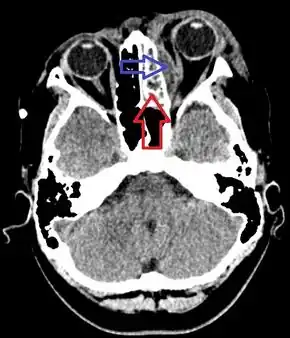

| Orbital cellulitis of the right eye | |

CT scan and MRI of the orbits are two imaging modalities that are commonly used to aid in the diagnosis and monitoring of orbital cellulitis, as they can provide detailed images that can show the extent of inflammation along with possible abscess location, size, and involvement of surrounding structures.[2] Ultrasound has also been used as an imaging modality in the past, but it cannot provide the same level of detail as CT or MRI.[2]